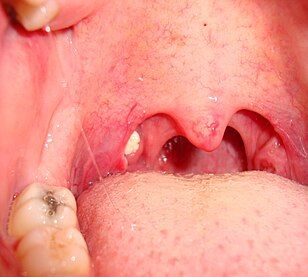

Keluarkan tahi mulut/batu tonsil

Batu tonsil (tahi mulut) boleh memerangkap bakteria dan menyebabkan mulut berbau amat busuk. Untuk mengeluarkannya, anda harus sentiasa berkumur menggunakan air garam. Jika tidak berjaya keluarkan, sila berjumpa dengan Pakar ENT untuk pertolongan.